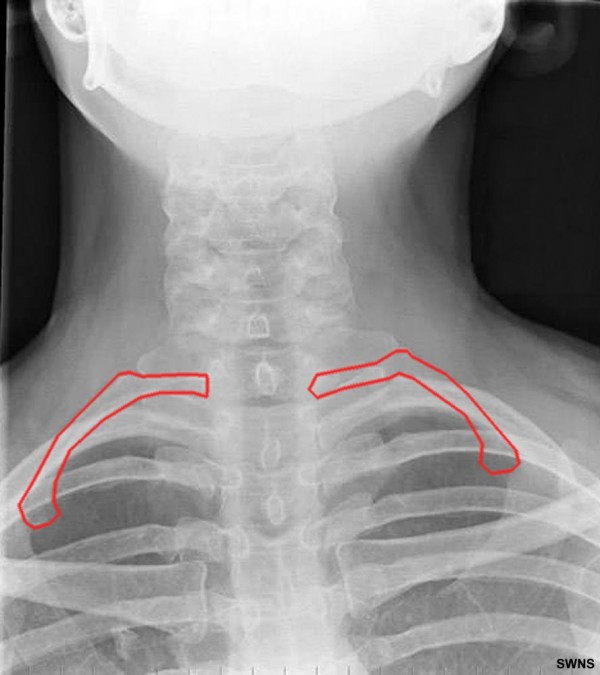

casa assistindo TV e tomando sorvete.4. Costelas a mais

Enquanto a maioria dos seres humanos tem 12 conjuntos de costelas, 0,5%

das pessoas e todos os chimpanzés e gorilas possuem um par extra perto

do pescoço. A porcentagem parece pequena, mas se você converter para

números absolutos, perceberá que 35 milhões de pessoas contam com mais

costelas do que deveriam.